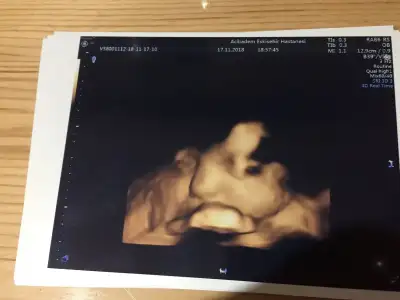

Oyyy minikkyaa bızım renklı pozlarımza bakın bugune dek bunları aldık 13haftalık biri dha 7cm orda

Bana da doktorum her gidişimde renkli görüntü verdi canım. Her defasında büyüdüğünü görmek çok güzel :)gecen bır arkadasıma da soyledım ankarada O. Ve gayet pahalı bır hastane. kadın renkli göstermemıs 17.haftada bıde dedım neden ses cıkarmıyorsun. ha şu da var benım hastaneme eşimın kuzenı gıdıyor o da daha alamamıstı onun dr.u baskası. nezaman verıyor dıye sordu bana benımkı verıyor dedım 13.haftadan buyana. dr.dan dr.a degısıyor demekkı canım![]()

evetttt yaaa resmen parmak kadarkenki halinden bebişliğe kadar olan sürecj göruyoruz nekadar şanslı bir donemdeyız kımbılır bızden sonra daha ne gelısmeler olacak şu teknolojide yerler onu pozlar hep aynı gb rahat glb ıcerde meleğinBana da doktorum her gidişimde renkli görüntü verdi canım. Her defasında büyüdüğünü görmek çok güzel :)